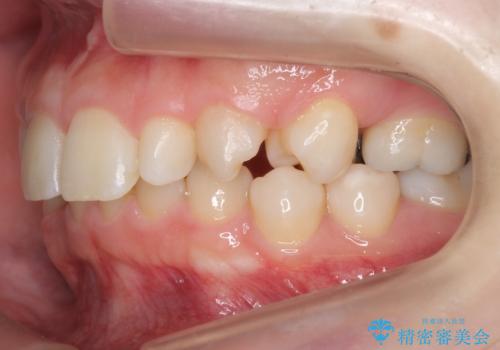

左右の前から2番目の歯が細く、矮小でした。

また、奥歯が2つ並んでおり歯ブラシがしにくい状態でした。

内側に入っている左上5を抜歯しています。